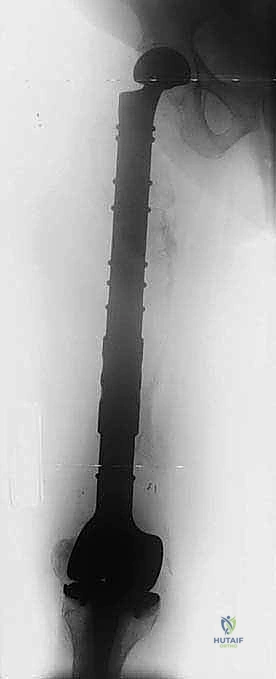

1. التثبيت الوقائي الداخلي (Prophylactic Internal Fixation)

إذا أظهرت الأشعة أن العظم ضعيف جداً وعلى وشك الانكسار، يقوم الدكتور هطيف بوضع أسياخ نخاعية معدنية (Intramedullary Nails) أو شرائح ومسامير متطورة داخل العظم لتدعيمه ومنع الكسر قبل حدوثه. هذه الجراحة الاستباقية توفر على المريض آلاماً مبرحة ومضاعفات خطيرة.

2. استئصال الورم وتغيير المفاصل (Tumor Resection & Endoprosthetic Arthroplasty)

في الحالات التي يدمر فيها الورم المفصل بالكامل (مثل مفصل الورك أو الركبة)، يقوم الدكتور هطيف باستئصال الجزء المصاب من العظم والورم معاً، واستبداله بمفصل صناعي خاص بالأورام (Megaprosthesis). بفضل خبرته الواسعة في تغيير المفاصل، يستطيع المريض المشي في اليوم التالي للعملية!

| عظم الفخذ (القسم العلوي) | كسر عنق الفخذ، العجز عن المشي. | استبدال مفصل الورك بمفصل صناعي (Arthroplasty). |

| جسم عظم الفخذ أو الساق | كسر مرضي كامل أثناء التحميل. | التثبيت بمسمار نخاعي تشابكي (Intramedullary Nailing). |